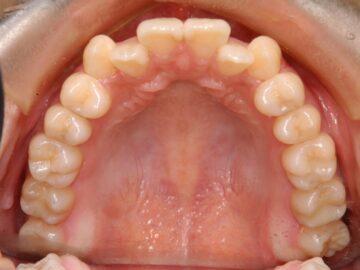

ご相談時

叢生(成人・自費治療・クリアタイプブラケット)

21歳 女性